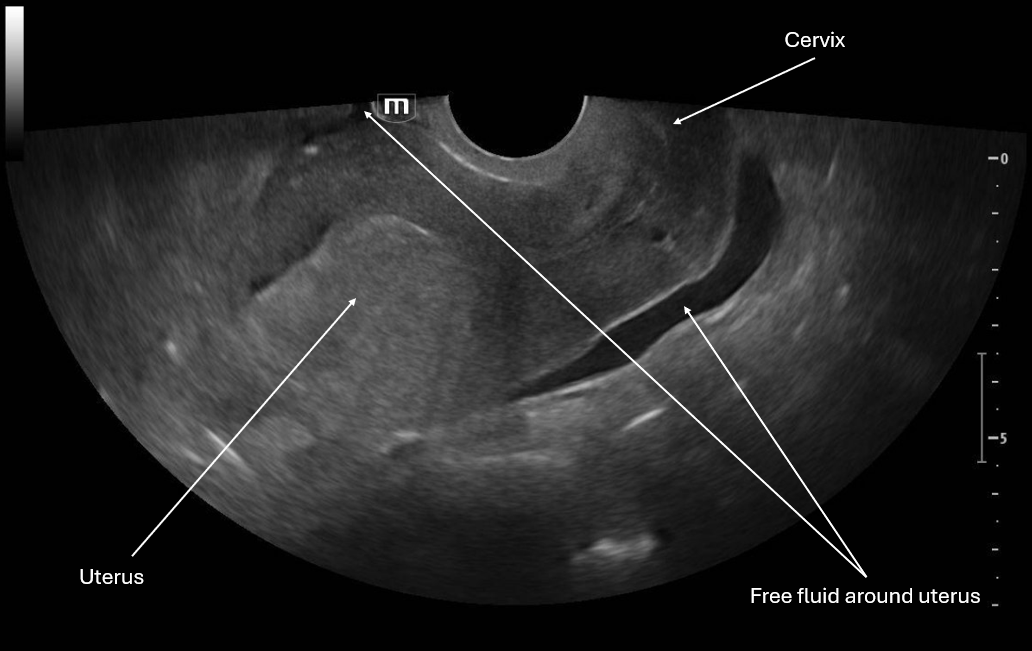

This image is a sagittal view of the uterus with the endocavitary probe marker directed up. From this we can see the fundus of the uterus and cervix with some pelvic free fluid extending past a third of the uterus.